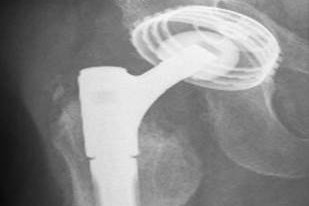

Bei sehr großen Knochendefekten im Beckenbereich kann ein individueller Beckenteilersatz geplant werden. Hierzu wird im Vorfeld eine dreidimensionale Computertomographie des Hüftgelenkes zur exakten Darstellung der knöchernen Verhältnisse angefertigt. Im Rahmen der Planung erfolgt eine präzise Anpassung des Implantates an die individuellen knöchernen Gegebenheiten unter Berücksichtigung von Beinlänge und Drehzentrum.

Aufgrund des hohen planerischen Aufwandes ist jedoch bis zur Operation eine längere Vorlaufzeit notwendig.